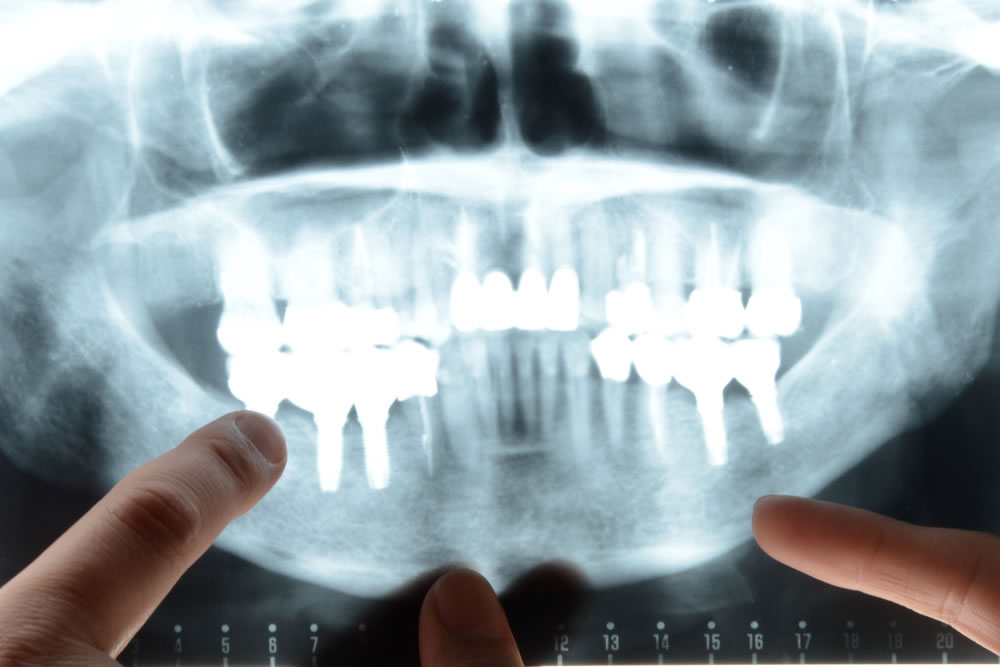

レントゲン撮影

歯の根っこの病気である根尖病巣や骨の吸収具合など、視診では見えない病巣の診断を行うために、レントゲン撮影を行います。